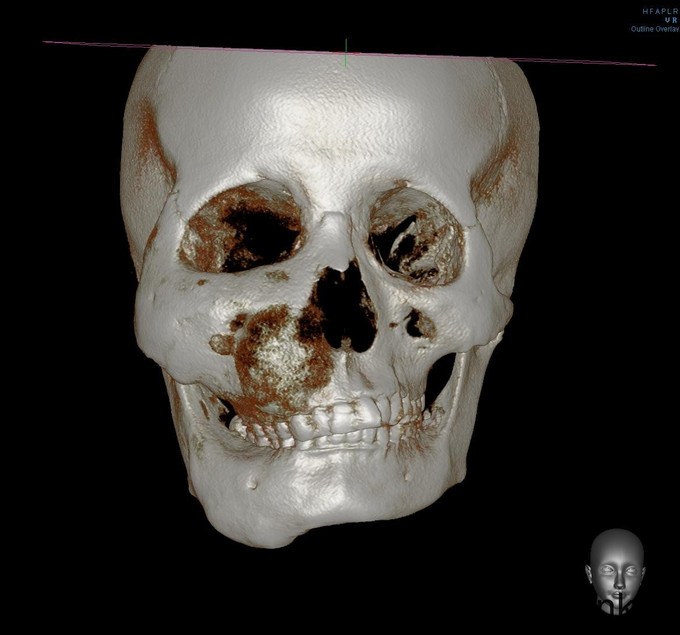

双侧颜面部不对称,右侧上下颌骨增大,质硬,双眼平视时存在复视,右眶下区、右下唇无麻木,右鼻无鼻塞,双侧髁突动度一致,开口度4cm,开口型正常,双侧颈部未扪及肿大淋巴结。口内检查:右下颌颊侧膨隆,右上颌颊侧、腭侧膨隆,余牙未见异常。CT示:右侧上、下颌骨、右侧颧骨、右侧蝶骨、蝶骨体、右侧额骨见明显膨胀性骨质破坏影,右侧髁突、冠突未见受累。骨破坏区边界大部分欠清,其内部密度高低不均匀,下颌骨病变处局部见类囊样低密影,余病变诸骨部分呈磨砂玻璃样密度影。病变区皮质菲薄、连续。右上颌窦、蝶窦窦腔完全闭塞。右侧鼻腔稍变狭窄,右侧眼眶底上抬。余左侧颌面诸骨未见明显骨质异常。诊断:右侧上、下颌骨、颧骨、右侧蝶骨、蝶骨体、右侧额骨骨纤维异常增殖症。